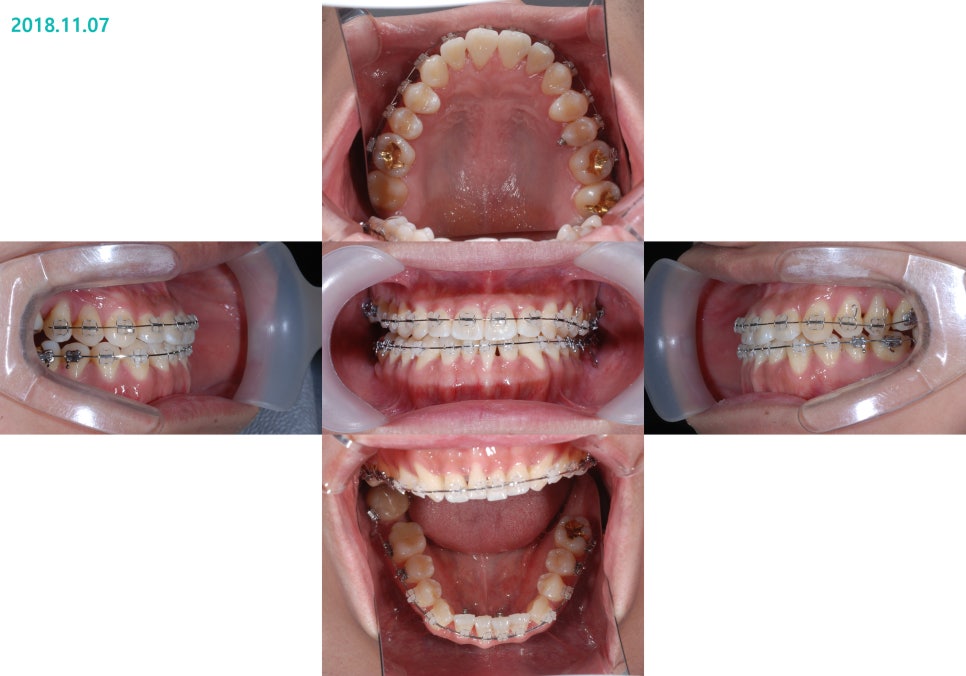

ºñ¼ö¼ú ºñ´ëĪ Ä¡¾Æ ±³Á¤ ÀüÈÄÀÇ »çÁøÀÔ´Ï´Ù.

½ÉÇÑ ÁÖ°ÆÅÎ, ½ÉÇÑ ¾È¸éºñ´ëĪÀÇ

ºñ¼ö¼ú ÁÖ°ÆÅÎ ±³Á¤Ä¡·á Àü

ºñ¼ö¼ú ÁÖ°ÆÅÎ ±³Á¤Ä¡·á ÈÄÀÔ´Ï´Ù.